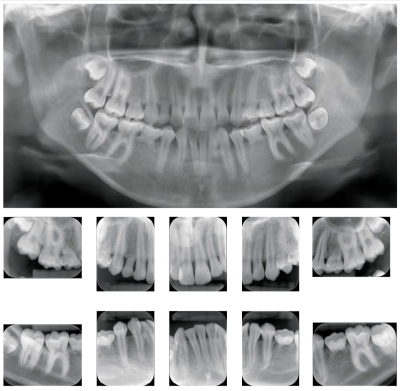

16 歳の女子。下顎の突出感と上顎右側乳犬歯の晩期残存を主訴として来院した。他に特記すべき既往はない。初診時の口腔内写真とエックス線画像を別に示す。先天欠如歯はどれか。1つ選べ。